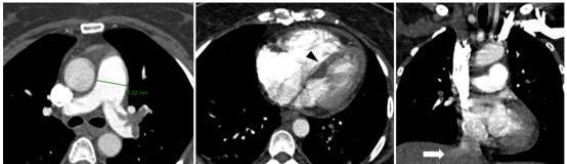

术后,排除手术相关因素后,结合患者的临床表现和术中症状,怀疑其发生了急性肺栓塞。进一步的诊断性检查明确了肺栓塞的诊断,结合CTPA(计算机断层扫描肺动脉造影)结果,显示大面积肺栓塞伴随右心室扩张和肺动脉高压。经胸超声心动图检查显示右心室负担加重,并伴有轻度的三尖瓣反流,肺动脉收缩压(PASP)达60mmHg。患者的D-二聚体水平显著升高,乳酸浓度也有所增加,这为肺栓塞的确诊提供了重要支持。